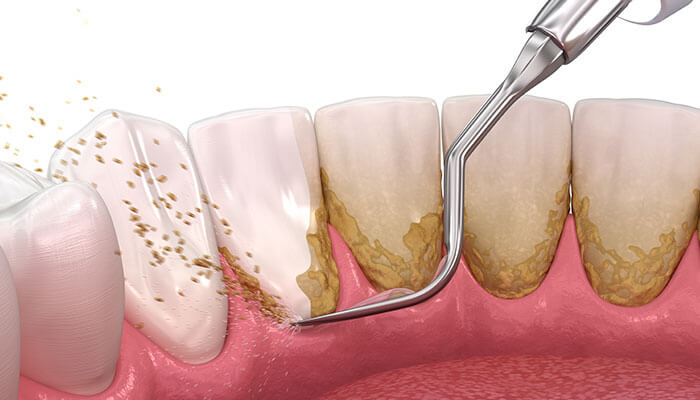

歯周病の原因はプラークですので、歯周病の重症度によらず、日々の歯磨き(ブラッシング)が最も重要な治療となります。軽度歯周炎で歯石が沈着している場合は、専用の機械・器具を使って歯石を除去します。

スケーリングとは歯に付着したプラークや歯石を除去する治療です。

歯石は歯面に付着したプラークに唾液中のリン、カルシウムが混じって石灰化したもので、表面は粗造でプラークが更に付着しやすいような構造をしており、歯に強固に付着しています。

スケーリングでは主に、超音波スケーラーやキュレットスケーラーを使用して取り除き、歯の表面をつるつるの状態にし、プラークが付着しにくい状態にします。

長期間、歯医者さんで歯石をとっておらず、歯石が多くついている状態になると歯と歯ぐきの境目の溝が4-6mmと深い状態になってしまいます。

この状態になると歯石が歯肉の中にまで付着してしまっているため、麻酔(表面麻酔、局所麻酔)などを用いて、歯石を除去して歯の根元をきれいにするSRPという処置が必要になります。この処置によって、ポケットが深い状態を改善することができます。深いポケットを放置すれば、その部分の歯周病は進行してしまいますので、しっかり歯石を除去することが大切です。